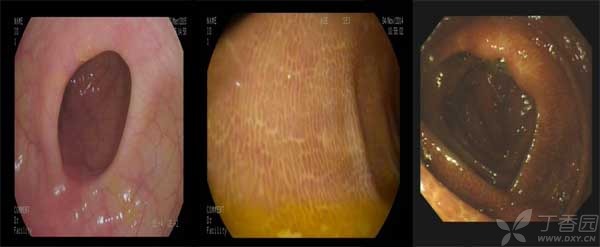

除了药物依赖问题,这种刺激会使色素沉着于肠壁,出现结肠黑变病,这种越洗越黑的洗澡,你我都不想看到吧?